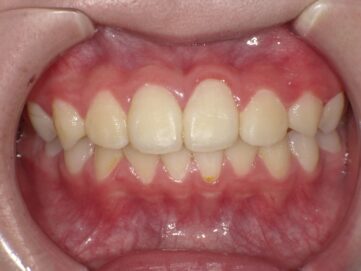

最近では歯並び・噛み合わせが悪い子供が増えてきています。成長期における生活環境や食生活による顎の成長不全が原因だと言われています。噛み合わせが悪いと歯がしっかりと生えることができなかったり、八重歯や出っ歯などの 不正咬合となってしまう可能性があります。

顎顔面矯正治療とは、歯並びだけでなく噛み合わせや顎関節を考慮して行う矯正治療のことです。顎顔面矯正治療により、顎関節症の緩和や鼻づまりの改善効果も期待できると言われています。主に、小児期に行い、見た目をよくするだけではなく、顎の骨や顔の骨格を正しい形に導きます。

歯並びの悪い原因としては顎の急な成長によるものが多く、装置で顎を広げる事で歯が綺麗に並ぶスペースを確保します。

青島歯科クリニックでは、顎顔面矯正治療によるお子さまの歯並びを綺麗に整える治療を行っており、お子さまの歯並びを骨格から正しく治し、成長を一緒にサポートさせて頂いております。